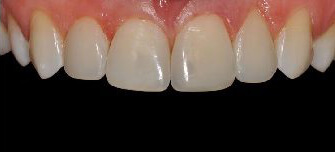

Проблема. Широкие промежутки между зубами и сколы на режущих кромках зубов.

Решение. Эстетическое пломбирование 4 зубов.